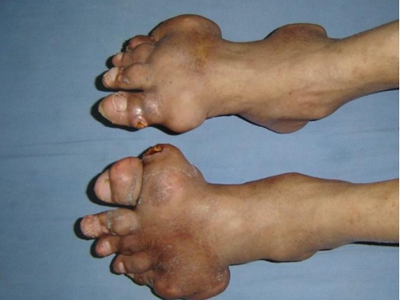

痛风病程较长,常反复发作而迁延不愈形成痛风石,是痛风的特征性临床表现,常见于指关节、第一跖趾关节、耳廓等处。外观为隆起、大小不一的不规则的黄白色赘生物,表面菲薄,破溃后排出白色粉状或糊状尿酸盐结晶物,经久不愈,但较少继发感染。部分患者伴有肾结石及肾脏病变。